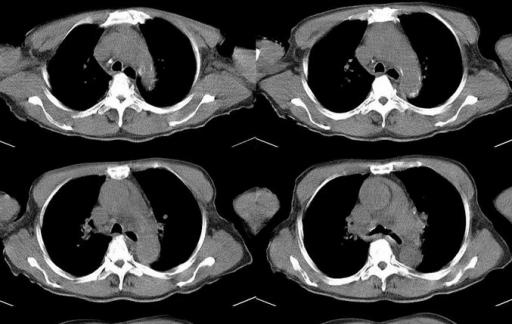

心脏心包积水又被称之为心包积液,它产生的主要症状为急性心包填塞症状。一般表现为循环衰竭。当发生急性的心包填塞时,患者可能会出现心跳过快,脉搏细弱,静脉压升高,动脉压下降。要是情况比较严重的话,很有可能会出现休克的状态,当然还会伴随大汗,心跳快,血压低,甚至,测不出具体的情况。

目前心脏心包积水主要分为急性心包积液和慢性心包积液,其中急性心包积液严重程度取决于积液形成的速度。

一旦出现以后,需要紧急解除心包积液对于心脏的压迫,常见的方式是进行心包穿刺,将积液引出。

而慢性心包积液形成的积液速度是比较缓慢的,因为心脏适应缓慢增加的积液,而心脏症状可能并不是特别的明显。但是长期慢性形成的心包积液可能会使后期回心血量减少,外周淤血情况加重。当然也有一些患者会出现外周浮肿,尤其是下肢。要是患者到了晚期心包积液,可能会有淤血性肝硬化,同时会长期低血压,也会产生众多的危害。